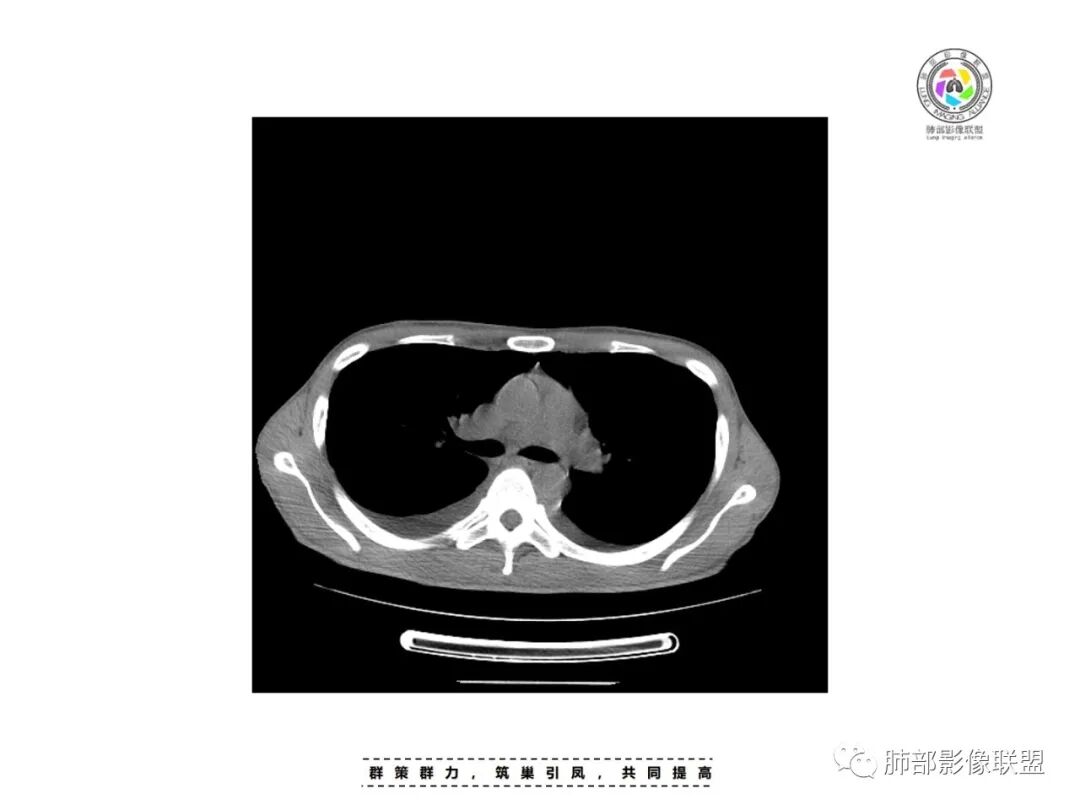

双侧胸水

心包积液

皮下轻微水肿

中轴间质增厚轻微

双下肺淡薄GGO

小叶间隔增厚

双侧胸腔积液,双下肺斑片状磨玻璃密度影,背景是大片状磨玻璃密度影,密度稍低一些。这个磨玻璃影非常弥漫,没有受局限,胸膜下不是很清楚,内部结构显示清楚,稍实变的区域也是,小叶间隔增厚,中轴间质也增厚。有些病变边缘有收缩,有轻度OP样特点,但是这些病变似乎密度非常均匀。

出血有可能,还要考虑到肺水肿,因为有胸腔和心包积液,小叶间隔也增厚。